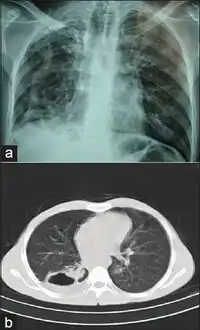

Infection